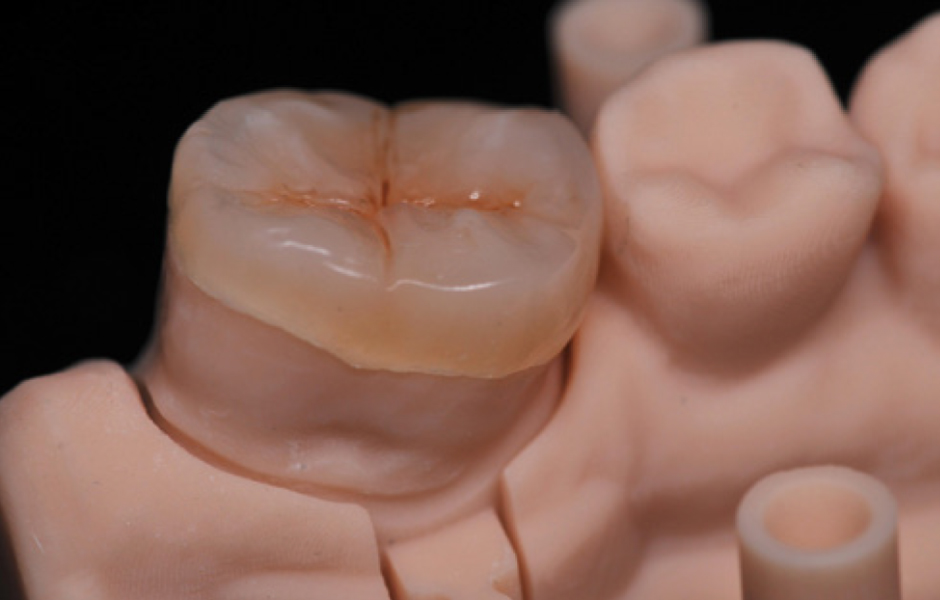

Obr. 6: Nepřímé rekonstrukce. Po dokončení výplní byly digitálně sejmuty otisky pomocí intraorálního skeneru Helios 500 (Eighteeth). Výhodou digitálního postupu je, že umožňuje dokončit rekonstrukci během jednoho dne. Finální nepřímá rekonstrukce byla totiž připravena k cementaci již o hodinu později.